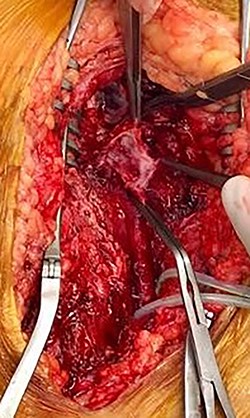

During operative intervention, a hematoma was observed involving muscle tissues in the anteromedial region of the thigh. There were no obvious signs of active infection. The proximal control obtained, the aneurysm incised and the distal control obtained. The aneurysm resected and samples collected for anatomopathological and microbiological analyses (Fig. 4). Reconstruction was performed by interposition of the ipsilateral great saphenous vein in reverse, with end-to-end anastomosis taking into consideration the diameter of the femoral artery (Fig. 5). Intraoperative tissue cultures were negative and the anatomopathological analysis showed a histopathological aspect corresponding to a PSA of the femoral artery, with the absence of the arterial wall and without specific character.